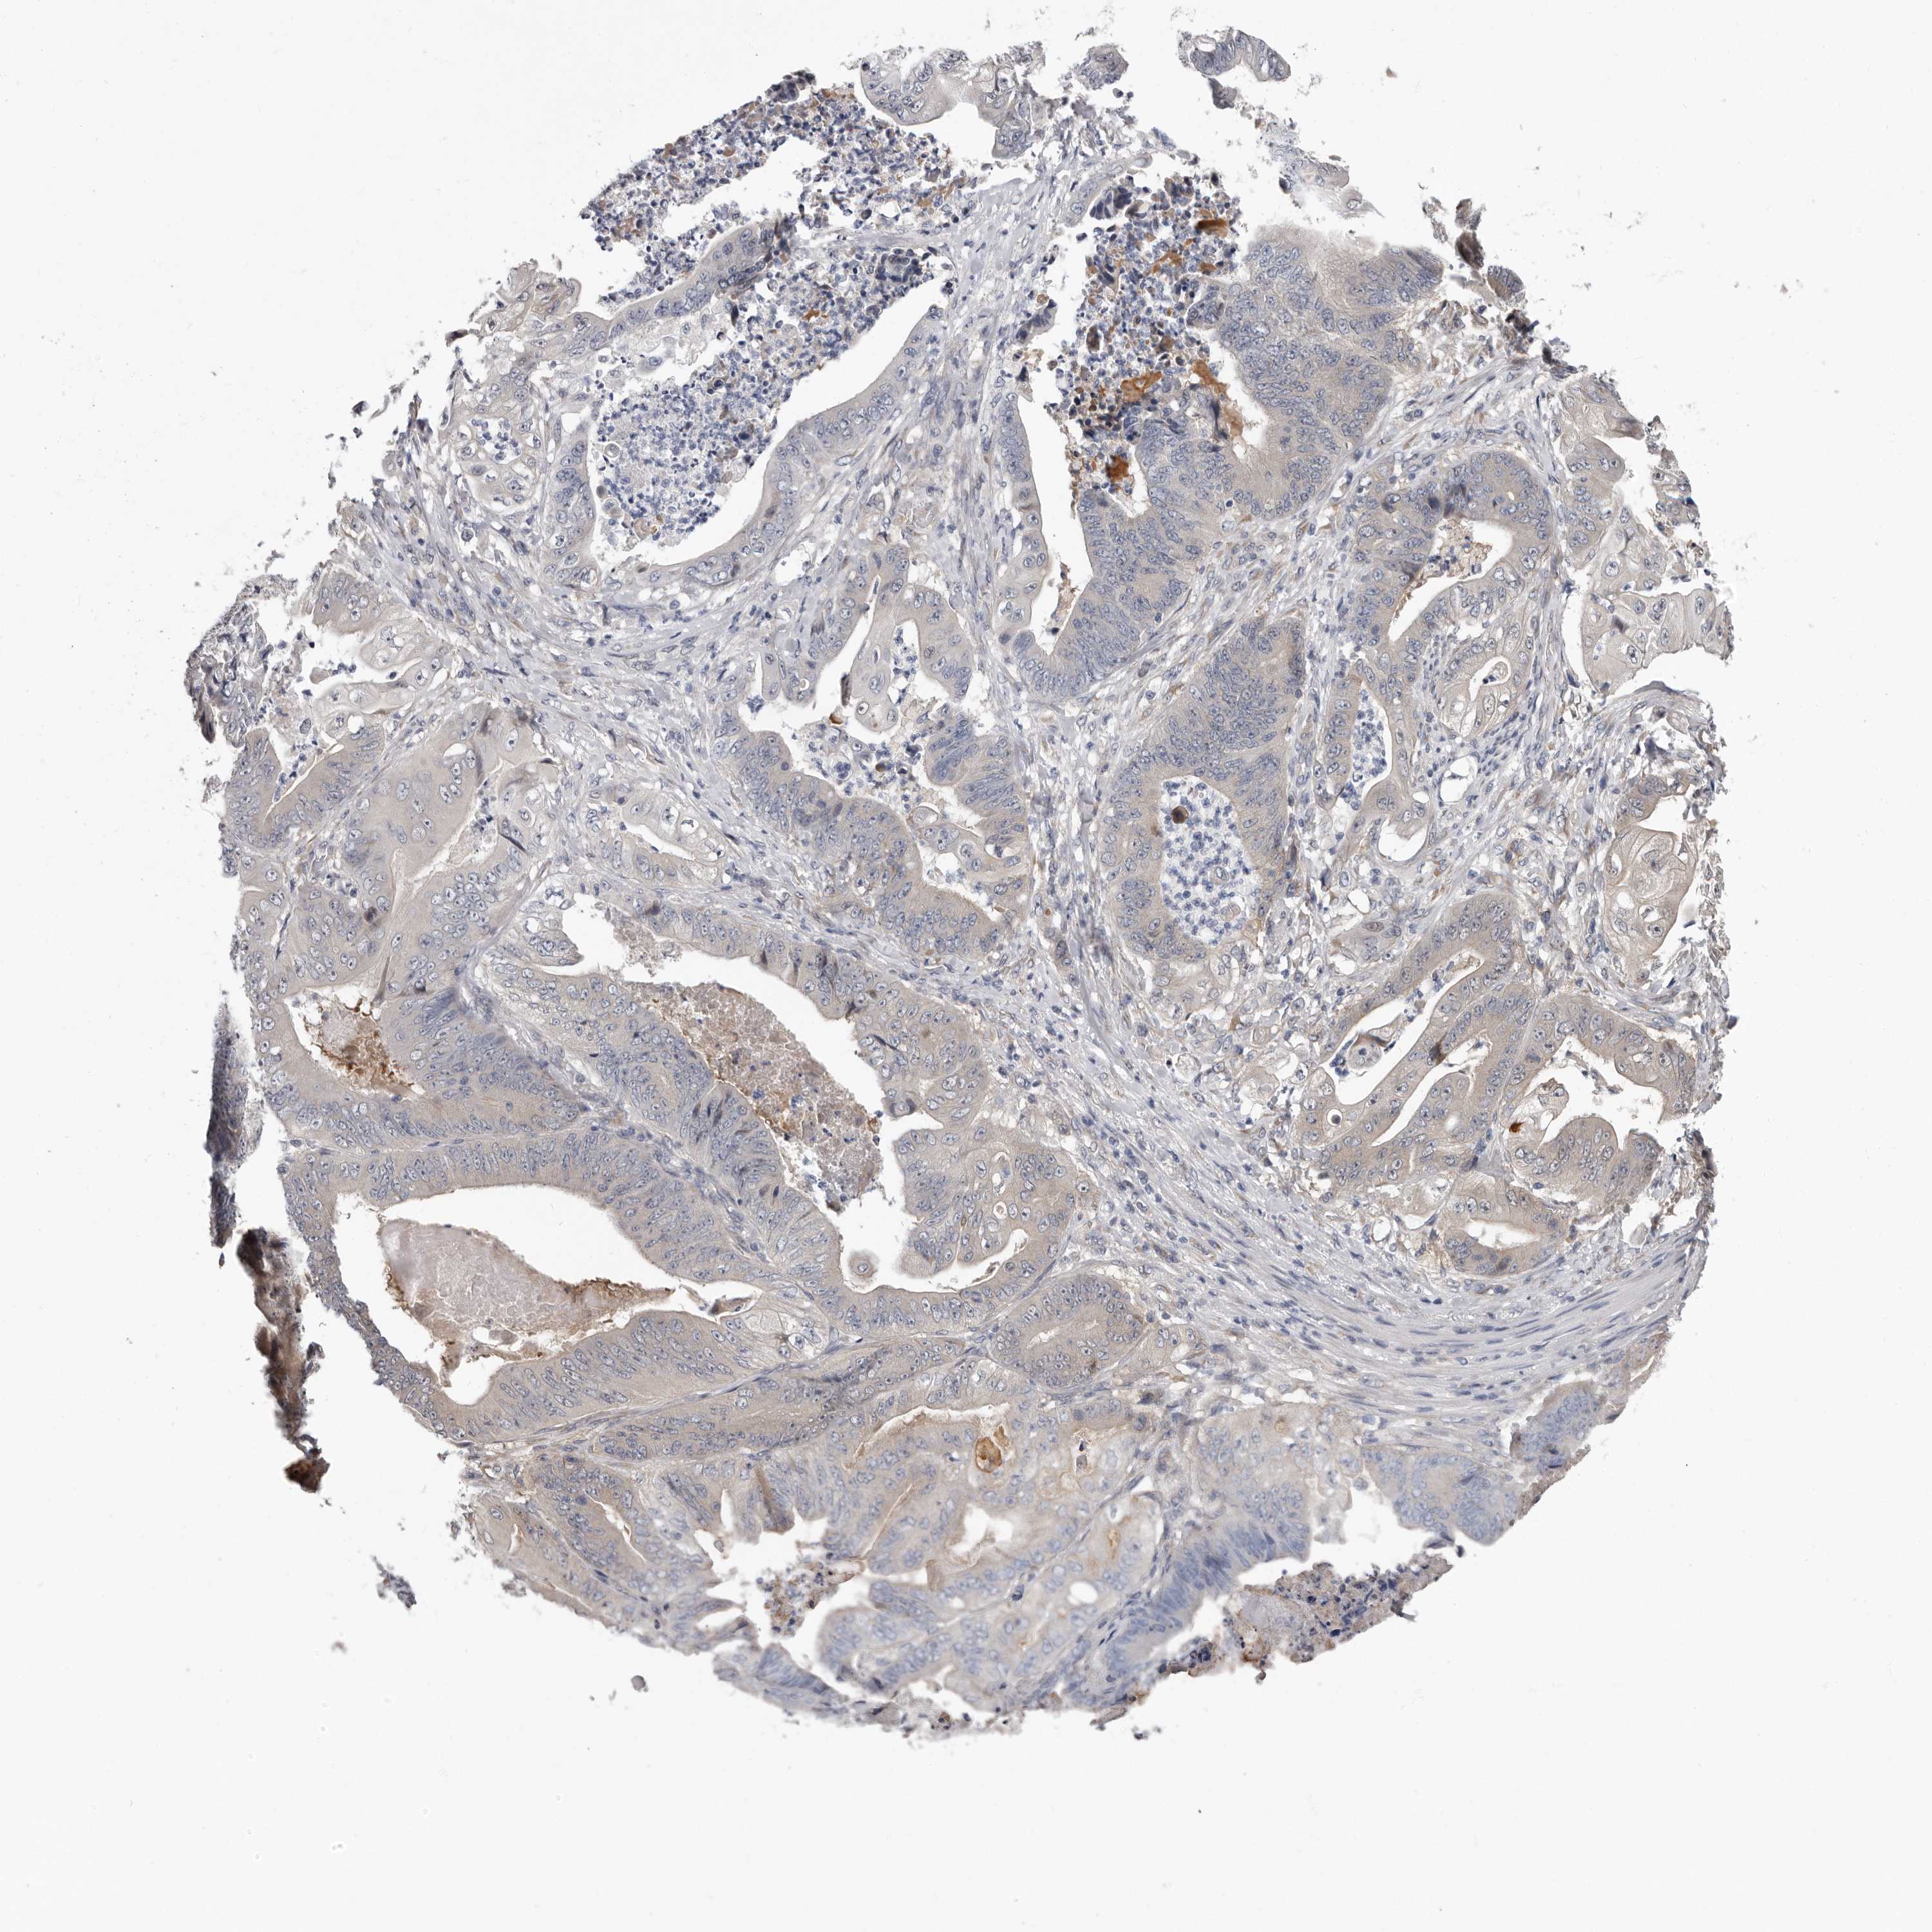

STOMACH CANCER - Protein expressioni

A mouse-over function shows sample information and annotation data. Click on an image to view it in a full screen mode. Samples can be filtered based on level of antibody staining by selecting one or several of the following categories: high, medium, low and not detected. The assay and annotation is described here.

Note that samples used for immunohistochemistry by the Human Protein Atlas do not correspond to samples in the TCGA dataset.

Antibody stainingi

Antibody staining in the annotated cell types in the current human tissue is reported as not detected, low, medium, or high, based on conventional immunohistochemistry profiling in selected tissues. This score is based on the combination of the staining intensity and fraction of stained cells.

Each image is clickable and will lead to virtual microscopy that enables deeper exploration of all samples and also displays staining intensity scores, fraction scores and subcellular localization as well as patient and tissue information for each sample.

Antibody HPA028377

Antibody HPA028438

Staining

High

Medium

Low

Not detected

Intensity

Strong

Moderate

Weak

Negative

Quantity

>75%

75%-25%

<25%

None

Location

Nuclear

Cytoplasmic/membranous

Cytoplasmic/membranous,nuclear

Adenocarcinoma, NOS